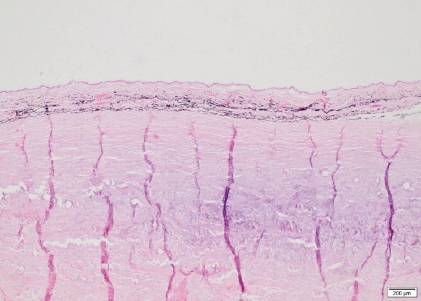

Both eyes showed no significant microscopic abnormalities of the anterior segment. All the retinal layers were preserved OD, including abundant ganglion cells. The retina OS was detached, with rounded edges at the periphery, consistent with a retinal tear. The central area of the retina OS was mainly composed of glial tissue and showed marked loss of all its layers (Fig. 6A). The peripheral retina OS preserved all its layers more frequently, but with occasional rosettes (Fig. 6B). Infrequent rosettes were also noted in the retina OS adjacent to the ONH. There was moderate gliosis of the ONH OS. Small mineral deposits were present peripapillary within the outer layers of the choroid OD. The posterior sclera immediately adjacent to the ONH showed chondroid metaplasia of the inner and mid layers OS (Fig. 7).

Axial globe lengths measured on US corresponded to measurements taken on histopathology. The axial globe lengths of case 1 were considered within normal limits OU when compared to published values (40.52 ± 2.67 mm) (Grinninger et al., 2010; Don, 2013). However, the axial globe lengths of case 2 were slightly increased OU while intraocular pressures were within normal limits (Miller et al., 1991; Michau, 2017). Furthermore, no signs consistent with glaucoma were detected on ophthalmic and histopathological examination, and thus the globe sizes of case 2 were considered as an anatomical variation. The continuously exposed sclera in case 2 was most likely the consequence of the globe size. In our patients’ eyes, histopathological examination revealed changes, more obvious OS than OD in both horses, and more severe in case 2 compared to case 1. The most pronounced abnormality was the detached retina OS associated with a retinal tear. The central detached retina did not show obvious neuronal components and was composed basically of glial tissue. The peripheral detached retina still contained some of the neuronal layers but also occasional small rosettes, although very sparse and embedded within the glial areas. These features are more consistent with retinal dysplasia with extensive areas of malformation or lack of development of the retinal layers rather than atrophy. These areas with absent layering are therefore probably part of the same congenital abnormalities. This is likely secondary to the retinal lesions previously described, or part of a more generalized vitreoretinopathy, in which an abnormal relationship between the retina and the vitreous may facilitate the detachment and tear. There was cartilaginous metaplasia of the central posterior sclera OS. This has been noted anecdotally as a degenerative change in aged horses but its significance in a young animal is difficult to determine. It has been described in Suffolk sheep but its clinical significance remains unknown (Smith et al., 2011). The presence of an incipient cataract OS was confirmed in case 2. No obvious features of a congenital cataract were noted, including duplication, wrinkling or irregular and frayed capsule, lysis of the nucleus, or vascular structures adhered to the lens capsule (Dubielzig et al., 2010). Therefore, it was interpreted as an acquired cataract, secondary to the RD.

Fig. 6. Detached retina OS, case 1. Central area of the retina mainly composed of glial tissue and marked loss of all its layers (A). Peripheral retina displays all its layers but marked disorganization is noted, with some rosettes formed by the outer nuclear layer extending into the inner nuclear layer consistent with retinal dysplasia (B) (H&E coloration, 100 µm).

Fig. 7. Sclera OS, case 1. Cartilaginous metaplasia in the inner and mid layers of the posterior sclera immediately adjacent to the optic nerve (H&E coloration, 200 µm).